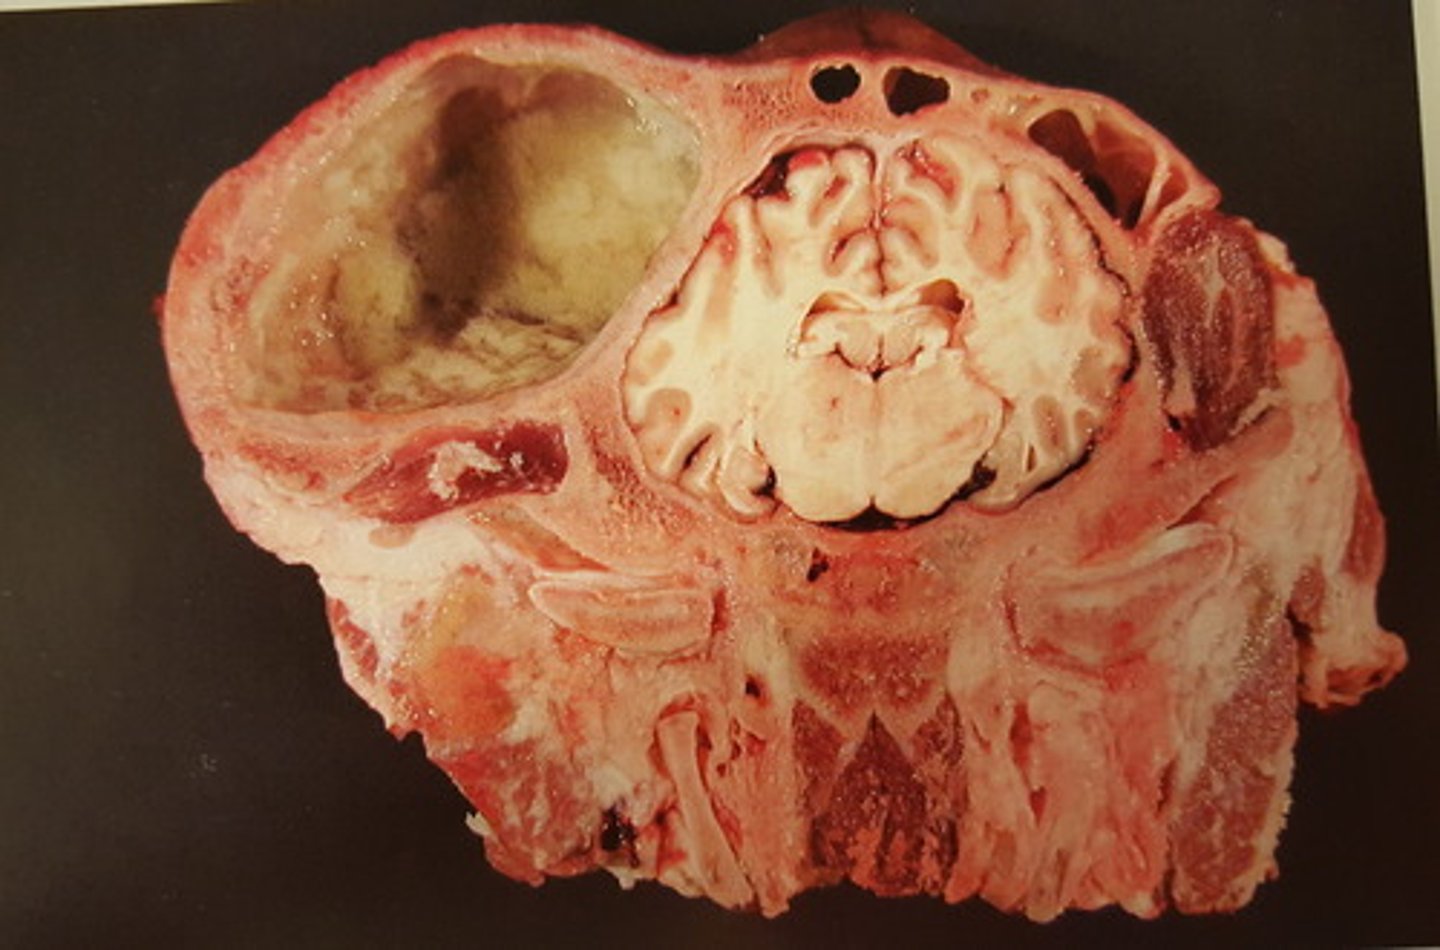

kronisk diffus pyocephali med dilation af ventrikelsystemet

Hjerne fra okse. Patoanatomisk diagnose?

hydrocephalus. Kan være BDV (bovin diarre virus)

Kollaps af resterne af cerebrum

Hjerne fra okse. Patoanatomisk diagnose? Hvad kan ætiologi være?